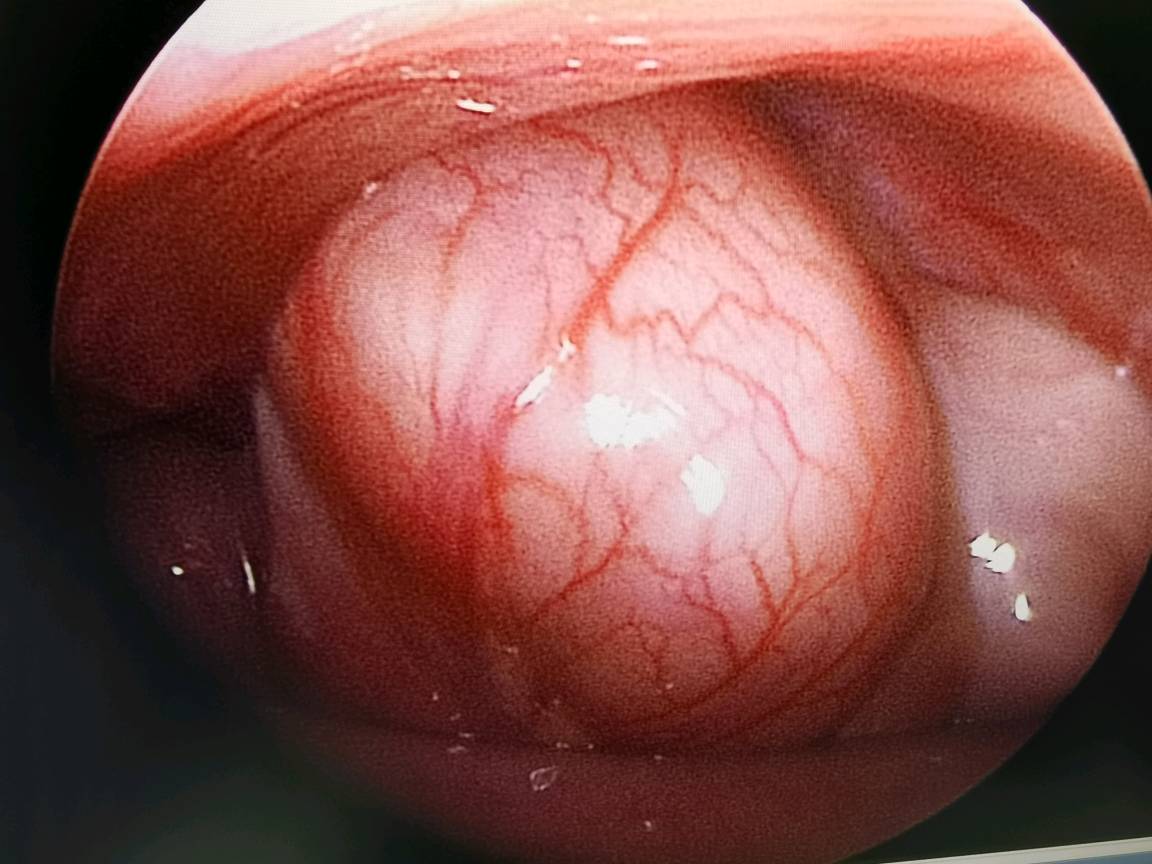

回盲部肠管嵌顿

鞘突管未闭